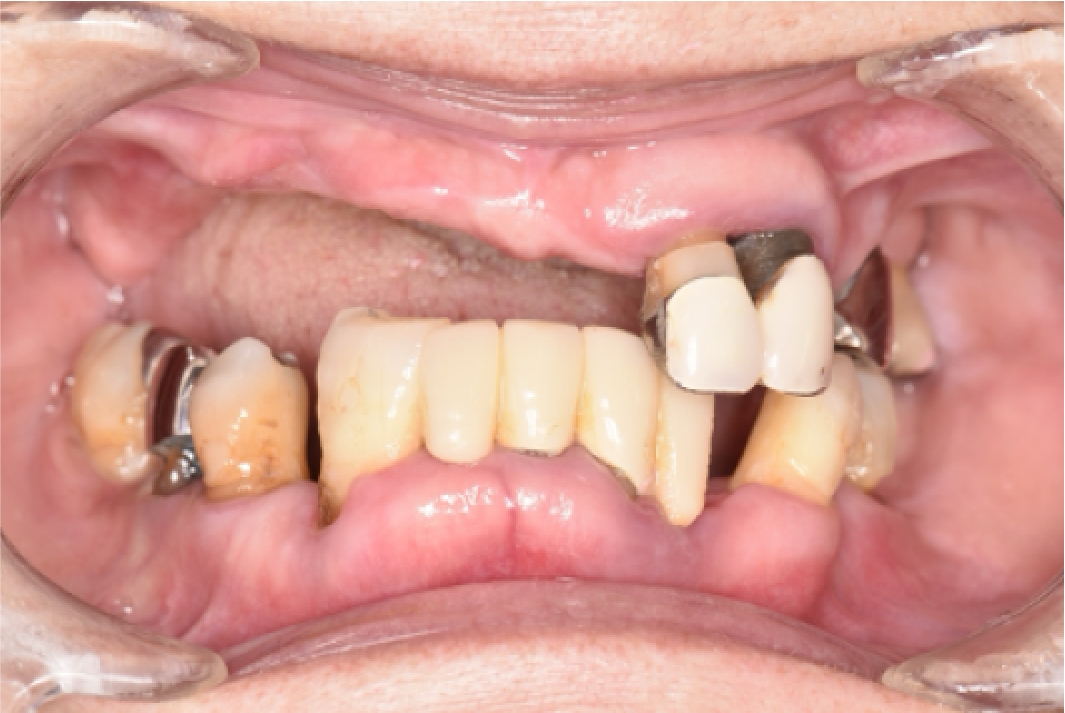

CASE02

■ 治療内容

上顎オールオン4インプラント治療(4本頬骨インプラント)

■ 治療費用

(モニター)3,330,000円(税込)

■ 治療期間

約10ヶ月

■ リスク

治療後の腫れや出血、またメンテナンスを怠ることで周囲炎のリスクあります。